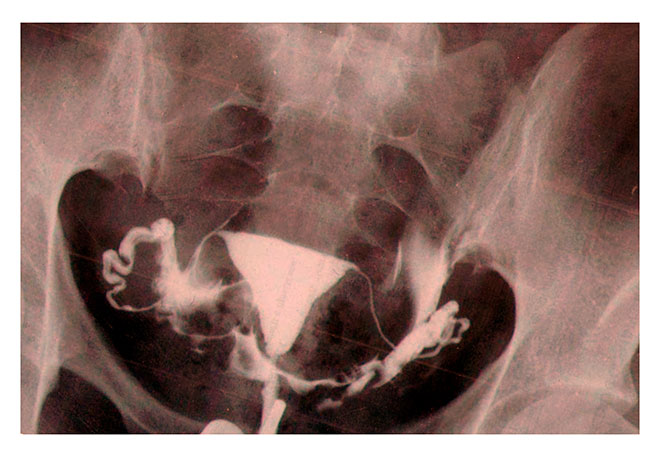

Чтобы с высокой точностью диагностировать спайки в малом тазу, женщине потребуется пройти сальпингографию или соносальпингографию. Сальпингография представляет собой рентгенографическое исследование. Маточные трубы пациентки заполняют специальным раствором, после чего выполняют несколько рентгенологических снимков. Благодаря раствору на них будут четко видны образования в придатках матки, если они там имеются. Сальпингографию проводят перед овуляцией. Это рекомендуется сделать для того, чтобы рентгенологические лучи не нанесли вреда здоровью плода, если вдруг произошло зачатие.